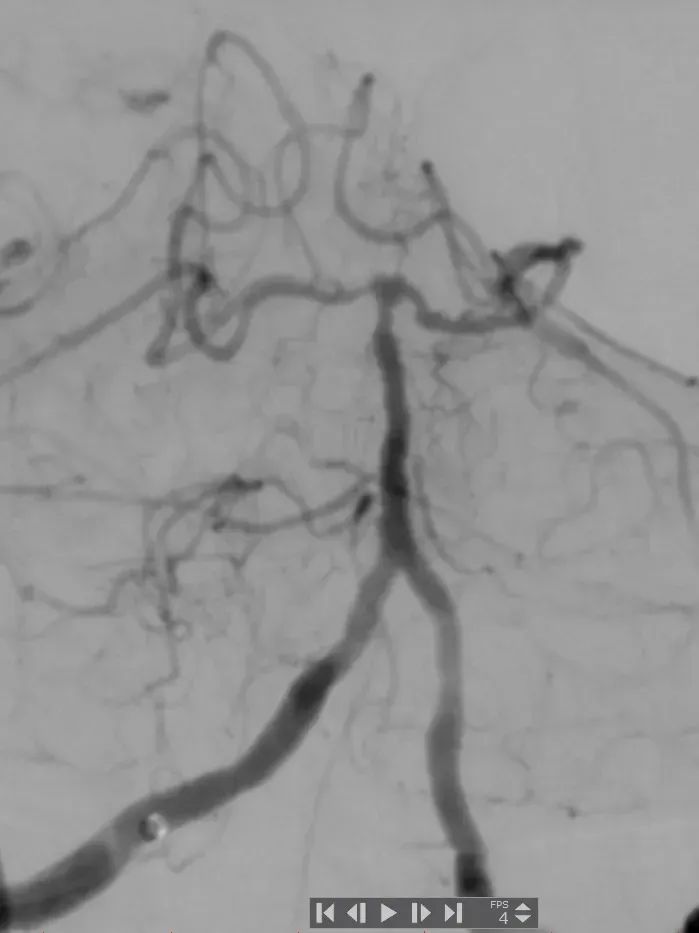

术后造影:基底动脉狭窄消失,双侧AICA通畅。

基底动脉狭窄位于双侧AICA开口处,且无双侧PICA,其供血区由双侧AICA、SCA分支代偿供血。

术中如何扩张基底动脉的同时保护双侧AICA通畅是手术成功的关键。

通桥银蛇®颅内支持导管具有优异的通过性,能够接近病变位置;具有优异的支撑性,为后续治疗器械的输送提供可靠的通路。